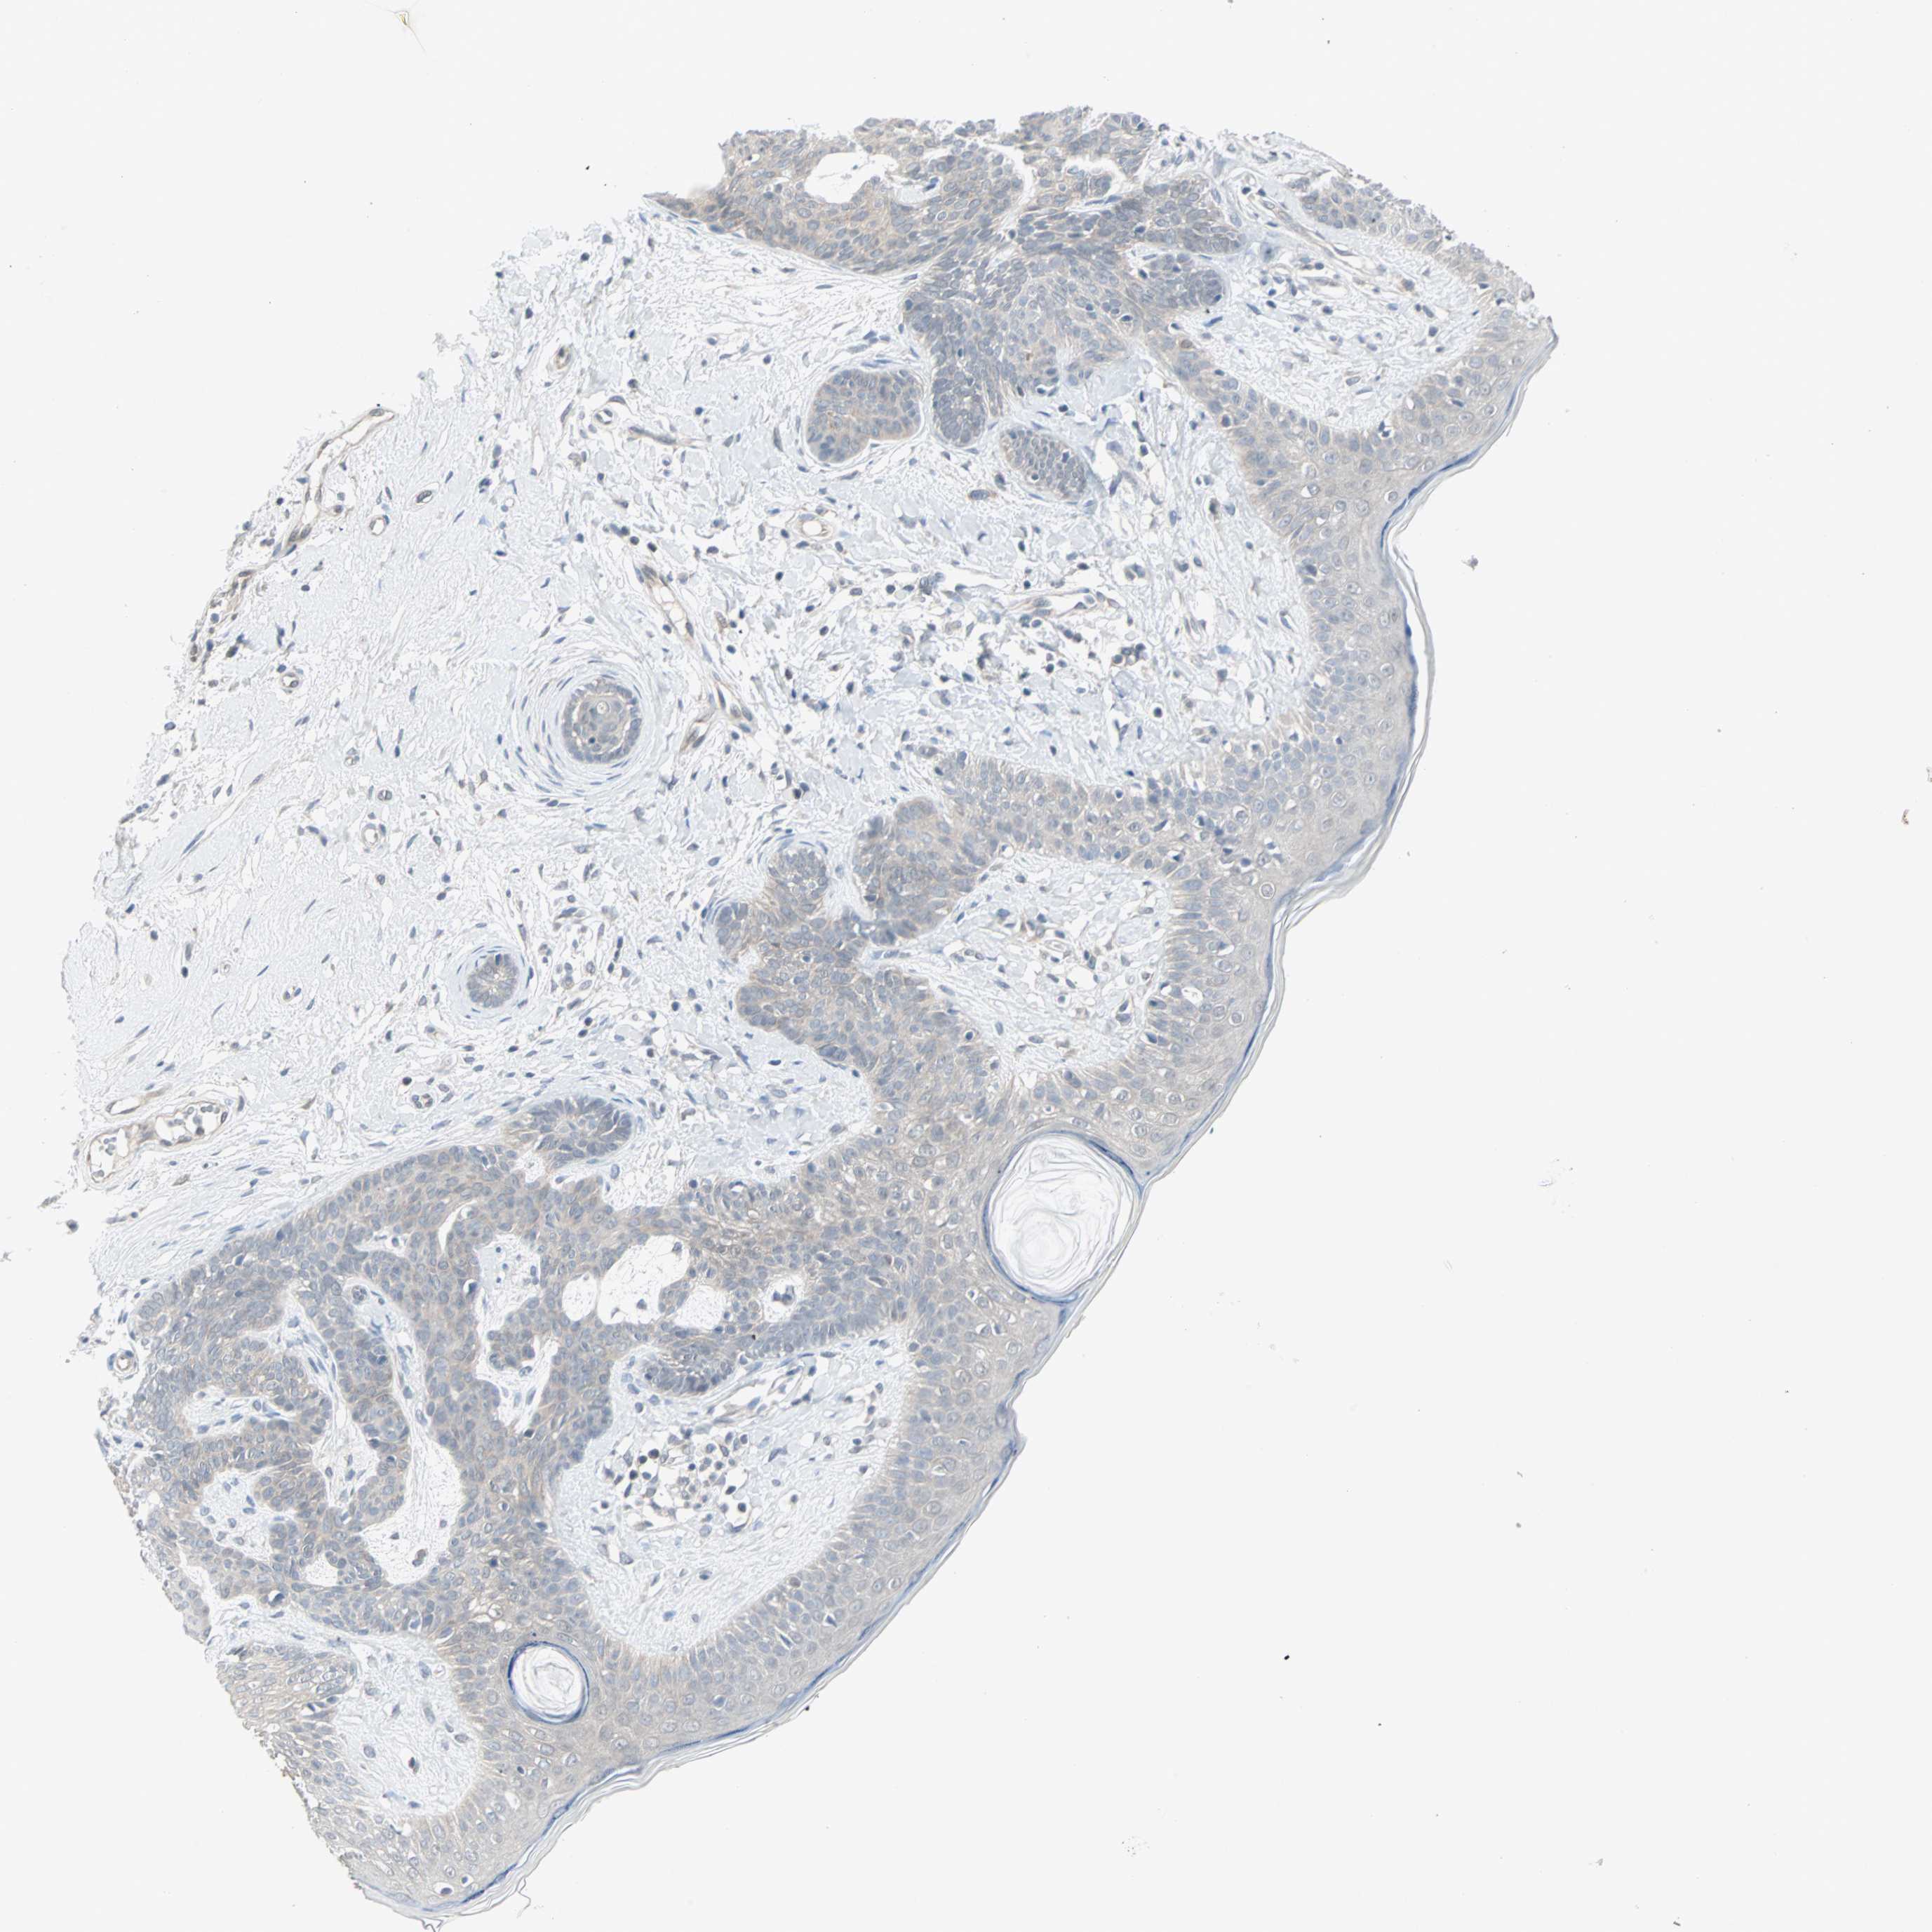

CANCER SKIN CANCER Show tissue menu

Basal cell and squamous cell cancer

SKIN CANCER - Protein expressioni

A mouse-over function shows sample information and annotation data. Click on an image to view it in a full screen mode. Samples can be filtered based on level of antibody staining by selecting one or several of the following categories: high, medium, low and not detected. The assay and annotation is described here.

Antibody stainingi

Antibody staining in the annotated cell types in the current human tissue is reported as not detected, low, medium, or high, based on conventional immunohistochemistry profiling in selected tissues. This score is based on the combination of the staining intensity and fraction of stained cells.

Each image is clickable and will lead to virtual microscopy that enables deeper exploration of all samples and also displays staining intensity scores, fraction scores and subcellular localization as well as patient and tissue information for each sample.

Squamous cell carcinoma, NOS

Squamous cell carcinoma, metastatic, NOS

Basal cell carcinoma

Papilloma, NOS